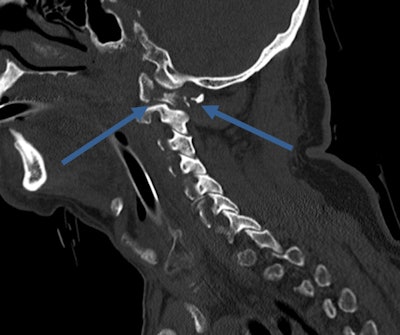

Because the population is aging, general radiologists are likely to come across geriatric trauma in regular routine practice. In the recent past, geriatric patients were often "underimaged," and the severity of injuries was likewise underestimated. Older people don't always complain even when they are in significant pain, explain trauma experts. Furthermore, mechanisms that would cause bruising in younger healthy adults, such as falling from a chair or from standing, can cause fractures and dislocations in geriatric patients.

"We must bear in mind that seemingly minor mechanisms may result in major injury, therefore we should have a low imaging threshold for whole-body CT in the elderly," said Dr. Elizabeth Dick, consultant radiologist and lead for emergency radiology at London's Imperial College NHS Trust. "Trauma teams should avoid piecemeal CT, focusing solely on the injured area. If the patient is stable, a whole-body CT should be performed whenever there is suspicion of significant injury, and don't delay."

"We often find numerous fractures from seemingly minor accidents. Despite a high scan rate in older patients, false-positive rates are low," noted Dick, who is also president of the British Society of Emergency Radiology.

Besides maintaining a high index of suspicion in elderly trauma patients, a deep knowledge of their injuries and syndromes can help radiologists avoid errors: There may be degenerative changes in the spine, such as central cord syndrome (CCS), bruising of the cord caused by compression of the canal space, usually undetectable on CT and requiring MRI.